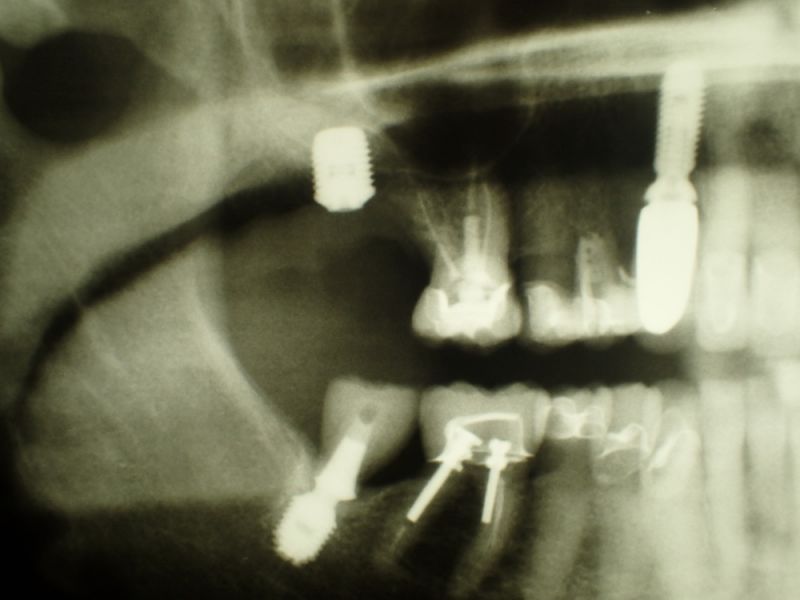

Bei der 80 jährigen Patientin wurde heute in regio 17 ein Implantat inseriert, mit dem Ziel der Wiederherstellung der linken Stützzone.

Wie man beispielhaft an diesem Fall sehen kann, geht der Trend in die Richtung selbst Patienten im fortgeschrittenen Alter weiter mit festsitzendem Zahnersatz zu versorgen, wenn der Patient das in der Vergangenheit so gewohnt war.

Kostentechnisch gesehen ist das sogar wesentlich preisgünstiger, als wenn man jetzt begonnen hätte mit hochwertigem herausnehmbarem Zahnersatz zu arbeiten.